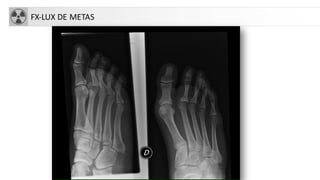

• Fracturas de los metatarsianos

• Más frecuente 5º meta

FX-LUX DE METAS